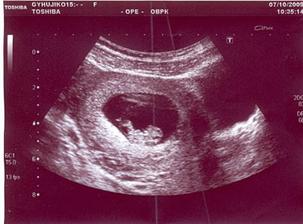

*1.9.2009 ... první TT

*20.9.2009 ... srdíčko

*20. - 28.9.2009 ... hospitalizace (špinění a krvácení)

*7.10.2009 ... 1. těhotenská poradna (vystavena těhotenská průkazka)